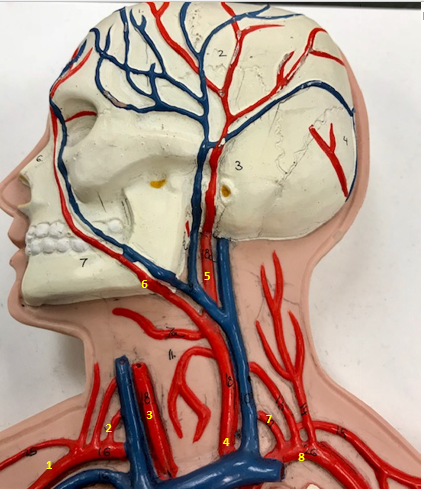

Right subclavian artery

Name #1

Supplies blood to right arm and shoulder

Function of right subclavian artery (1)

Right vertebral artery

Name #2

Supplies blood to brain and spinal cord

Function of right vertebral artery (2)

Right common carotid artery

Name #3

Supplies blood to right neck and head

Function of right common carotid artery (3)

Left common carotid artery

Name #4

Supplies blood to left neck and head

Function of left common carotid artery (4)

Left external carotid artery

Name #5

Supplies blood to face neck and skull

Function left external carotid artery (5)

Left facial artery

Name #6

Supplies blood to face and neck

Function of left facial artery (6)

Left vertebral artery

Name #7

Supplies blood to brain and spinal cord

Function of left vertebral artery (7)

Left subclavian artery

Name #8

Supplies blood to left arm and shoulder

Function of left subclavian artery (8)